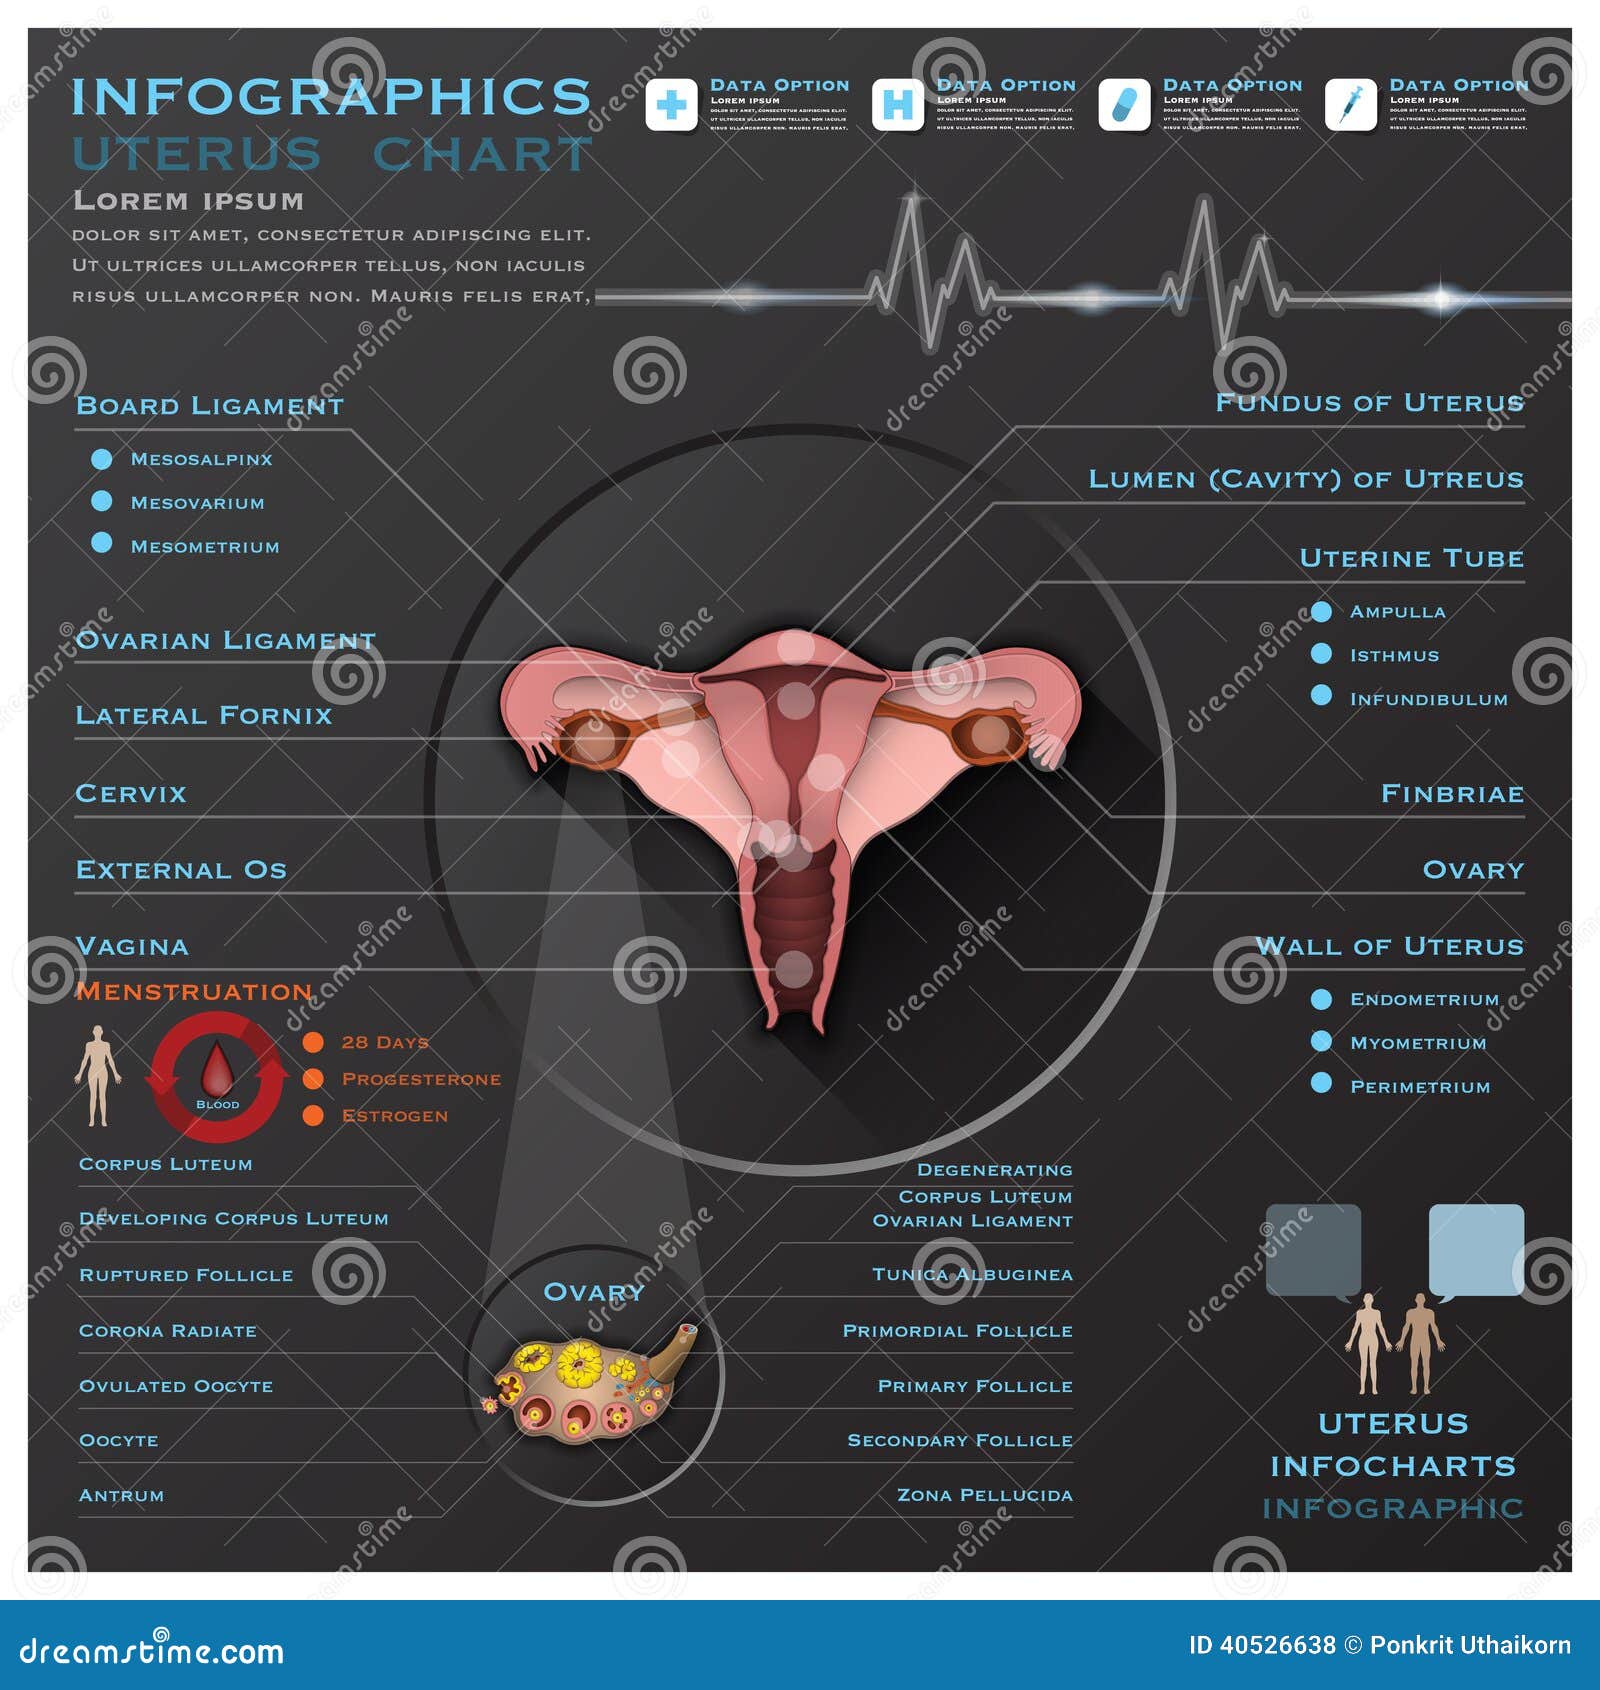

Ovary Anatomy Royalty Free Stock Photo CartoonDealer 84221631

Uterus And Ovaries Internal Organs Of Human 17415553 PNG